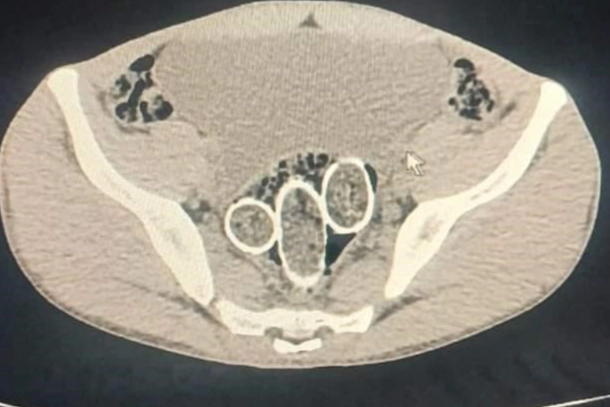

Denizli İl Emniyet Müdürlüğü Narkotik Suçlarla Mücadele Şube Müdürlüğü ekiplerince, uyuşturucu ticaret yapan şahıs veya organizasyonların yakalanmasına yönelik operasyon düzenlendi. Düzenlenen eş zamanlı operasyonlarda 5 şüpheli şahıs yakalanırken, iki şahsın yaptırılan iç beden muayenesinde ve kullandıkları iki araçta yapılan incelemelerde rahimde ve midede uyuşturucu madde tespit edildi.

Operasyonda 6 parça halinde 320 gram metamfetamin maddesi, 1,6 gram afyon sakızı maddesi, uyuşturucu madde ticaretinden elde edildiği değerlendirilen 114 bin 430 TL, 12 bin 595 Euro, 300 dolar, 1 adet sahte pasaport ele geçirildi. Ayrıca yakalanan şüpheli şahıslardan 1 şahsın 6 yıl 8 ay kesinleşmiş hapis cezası ve 16 bin 600 TL adli cezası ile arandığı tespit edildi. Yakalanan şüpheli şahıslar, “Uyuşturucu Madde Ticareti Yapmak” suçundan adli makamlara sevk edilen 2 şüpheli şahıs hakkında adli kontrol kararı verilirken; 3 şüpheli şahıs ise tutuklanarak cezaevine gönderildi.